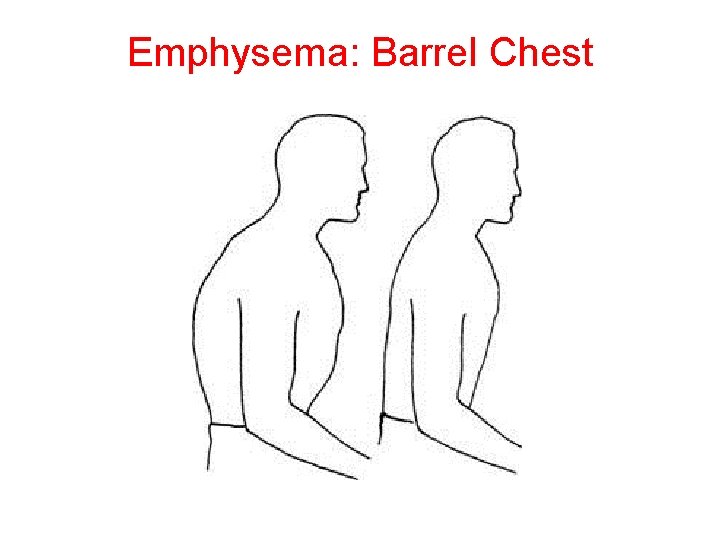

Emphysema: Barrel Chest